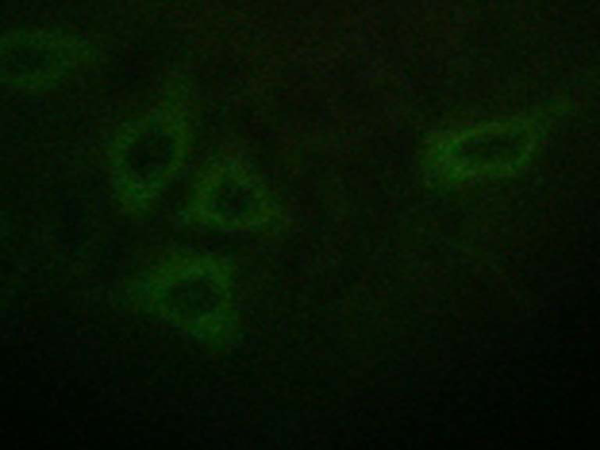

IF positive control: |

HepG2 cells |

IF Recommend dilution: |

100-500 |